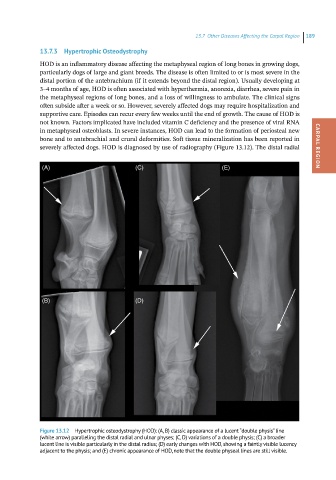

severely affected dogs. HOD is diagnosed by use of radiography (Figure 13.12). The distal radial CARPAL REGION

Figure 13.12 Hypertrophic osteodystrophy (HOD): (A, B) classic appearance of a lucent “double physis” line

(white arrow) paralleling the distal radial and ulnar physes; (C, D) variations of a double physis; (C) a broader

lucent line is visible particularly in the distal radius; (D) early changes with HOD, showing a faintly visible lucency

adjacent to the physis; and (E) chronic appearance of HOD, note that the double physeal lines are still visible.